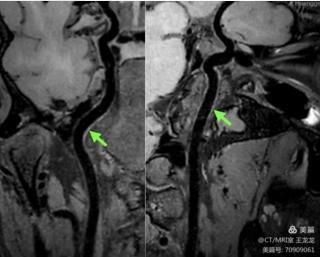

颈内动脉斑块内出血